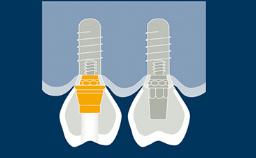

As próteses fixas implantossuportadas visam fornecer substitutos para dentes ausentes que são capazes de resistir à demandas funcionais e imitar com acurácia a estética das unidades denteais ausentes. Idealmente, a prótese deve ser indistinguível da dentição ao redor. Para atingir este objetivo, o clínico deve selecionar os melhores materiais disponíveis para enfrentar os desafios da situação clínica. Este módulo discutirá os materiais dentários disponíveis para a fabricação de próteses implantossuportadas e os princípios básicos envolvidos na seleção do material mais adequado para cada caso.